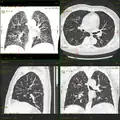

Iterative Korrektur in der Computertomografie: 1 mm Schichtdicke, 120 kV, 20 mAs. Links gefilterte Rückprojektion, Mitte iterative Korrektur erste Generation, rechts iterative Korrektur modellbasiert. Insbesondere bei wenig Dosis und dünnen Schichten ist die deutliche Reduktion des Rauschens im Bild gut zu erkennen. Hier apikaler Pneumothorax rechts.